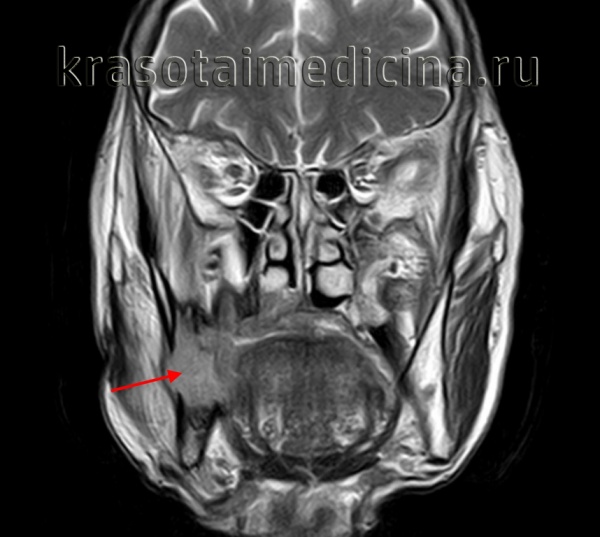

(Слева) На панорамной рентгенограмме в нижней челюсти слева определяется крупная у ни кистозная амелобластома, хорошо отграниченная кортикальной пла стинкой на периферии. Амелобластома выглядит многокамерной из-за фестончатых краев. Обратите внимание на вовлечение венечного отростка. Также определяется смещение треть его моляра с резорбцией корня.

(Справа) На аксиальной КТ с КУ у этого же пациента определяется вздутие кортикальных пластинок. Низкая плотность образования позволяет предположить кисту, однако контрастирующийся муральный узел является ключом к правильному диагнозу.